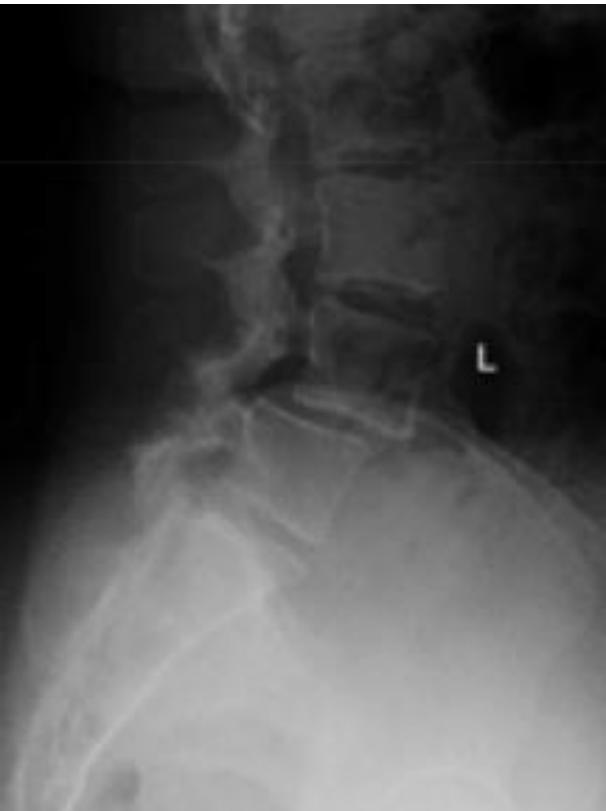

Degenerative Spondylolisthesis

- Definition: Common degenerative condition characterized by subluxation of one vertebral body anterior to the adjacent inferior vertebral body with intact pars

- Demographics: Most common in females over 40 years of age, at the L4-5 level

- Diagnosis: Lateral radiographs; flexion and extension lateral lumbar radiographs can identify degree of instability

- MRI: Helpful for central or foraminal stenosis